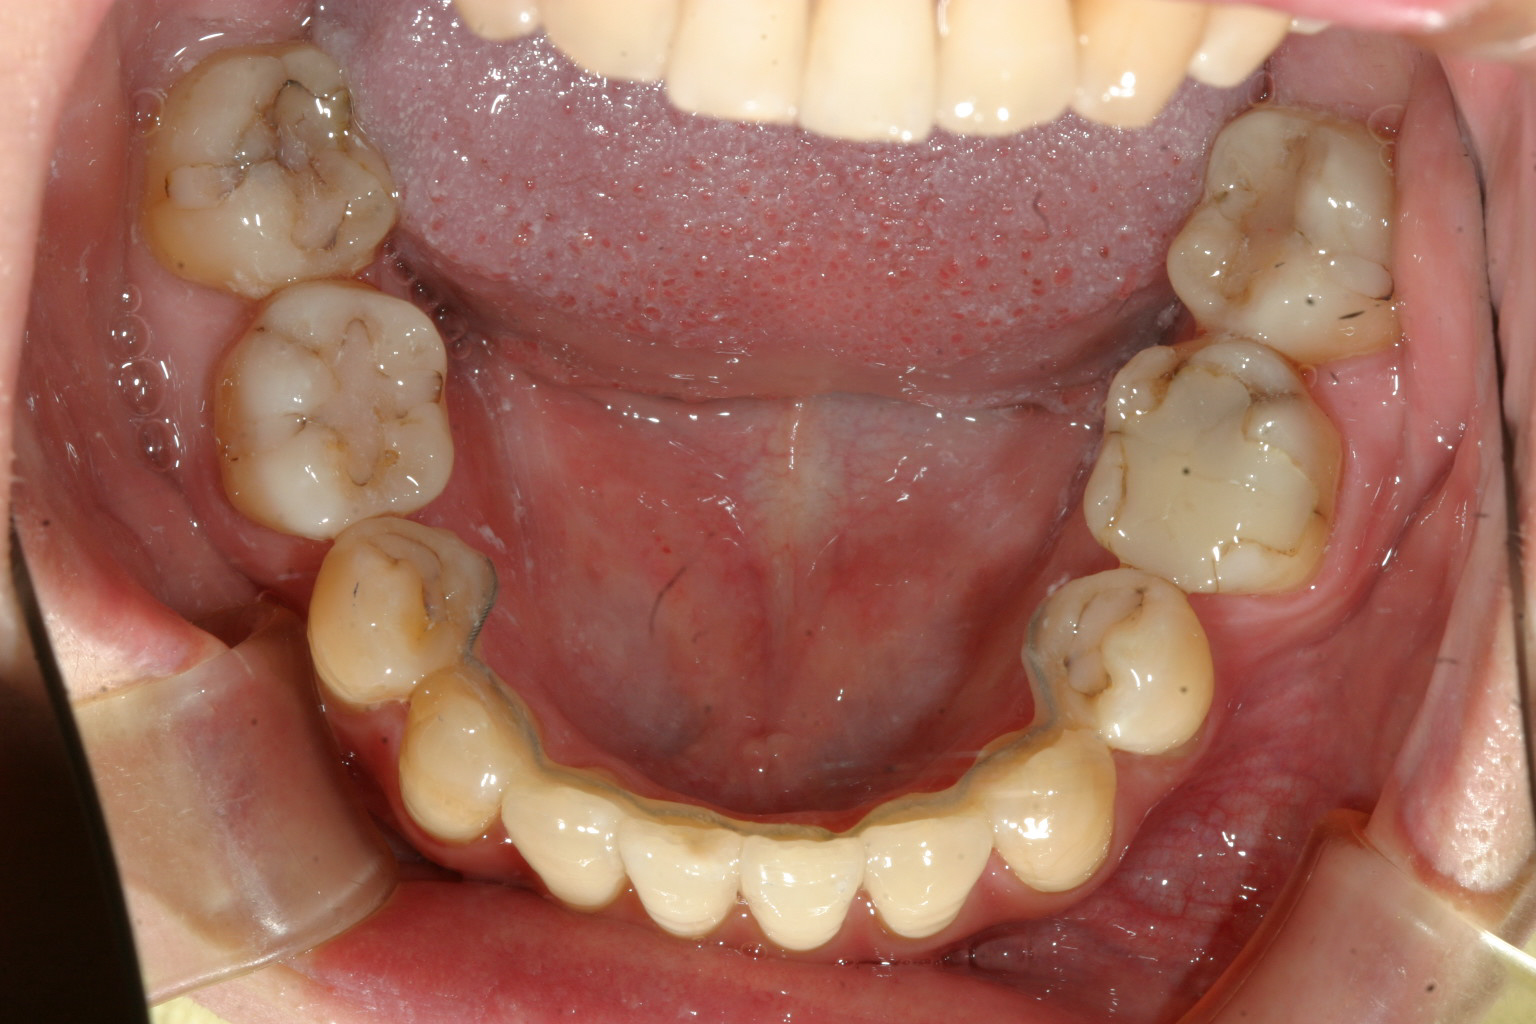

下顎も抜歯スペース綺麗に閉じました。

上下左右の小臼歯抜歯してインビザラインと加速矯正装置利用で矯正しました。

かなり綺麗に仕上がりました。

途中で抜歯スペース閉鎖する時に後ろの歯が前に倒れて来て立てるのに部分ワイヤー矯正も併用し少し時間を食いましたが一切追加費用無しで終了しました。